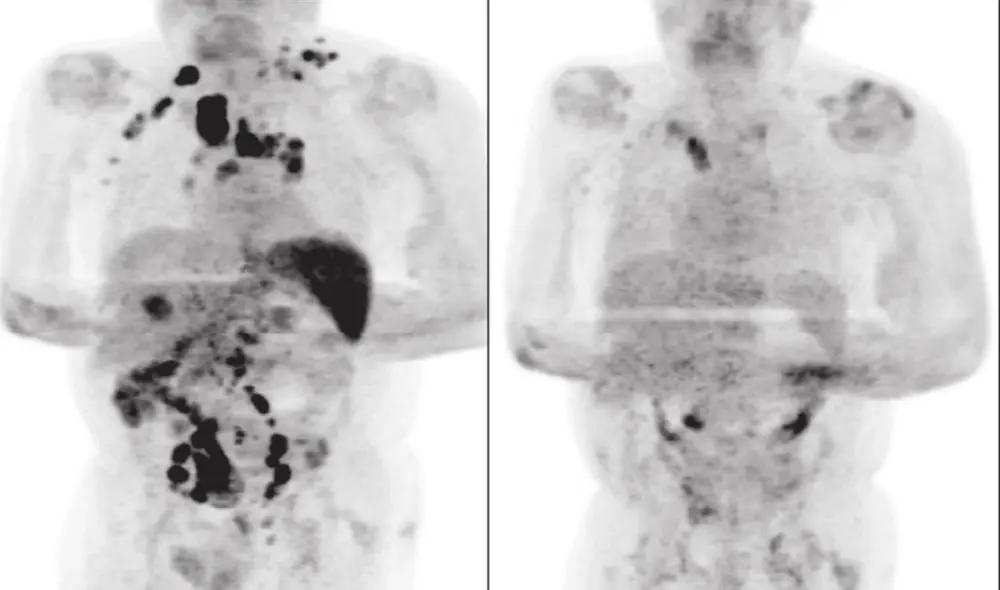

Cuatro meses después, notaron que la inflamación de los ganglios se había reducido y una exploración por tomografía PET reveló una remisión generalizada del linfoma. El cáncer había retrocedido notablemente.